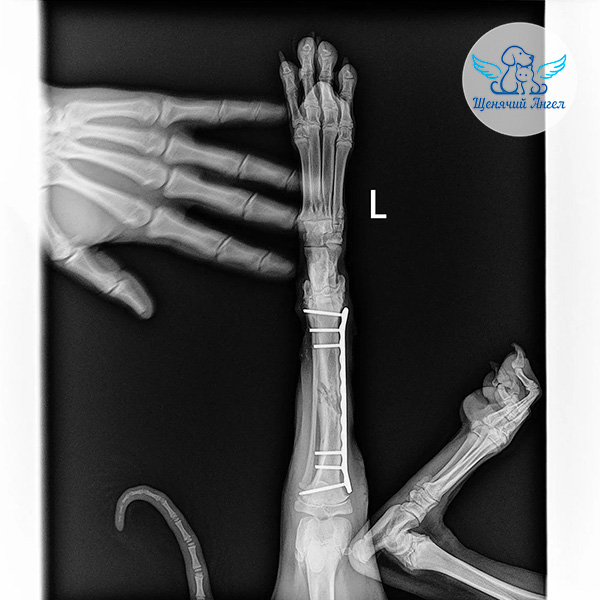

🩻 Рентген показал перелом голени левой задней лапы. Кроме того, на фоне травмы у Джоя открылось кровотечение в желудочно-кишечном тракте. К счастью, его удалось остановить медикаментозно.

После проведения необходимых обследований Джою выполнили операцию – остеосинтез на повреждённой лапе.

Во время хирургического вмешательства врачи зафиксировали перелом с помощью специальных металлических конструкций, чтобы кость могла правильно срастись 🐾